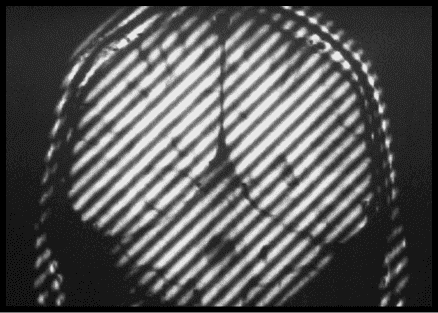

he so-called [herringbone or spike MRI artifact][1] on a given example could be traced to a specific point(s) in Fourier space ("k-space").

The idea is that during the acquisition of the image, a certain RF wave emitted by the patient (providing the info about diseased or normal anatomy) had become distorted by some extraneous RF interference, and sampled as such through a DFT process into Fourier space (k space). After producing the reverse FFT, that dot of artifact affected the whole image in a striped pattern:

sUbsh.png